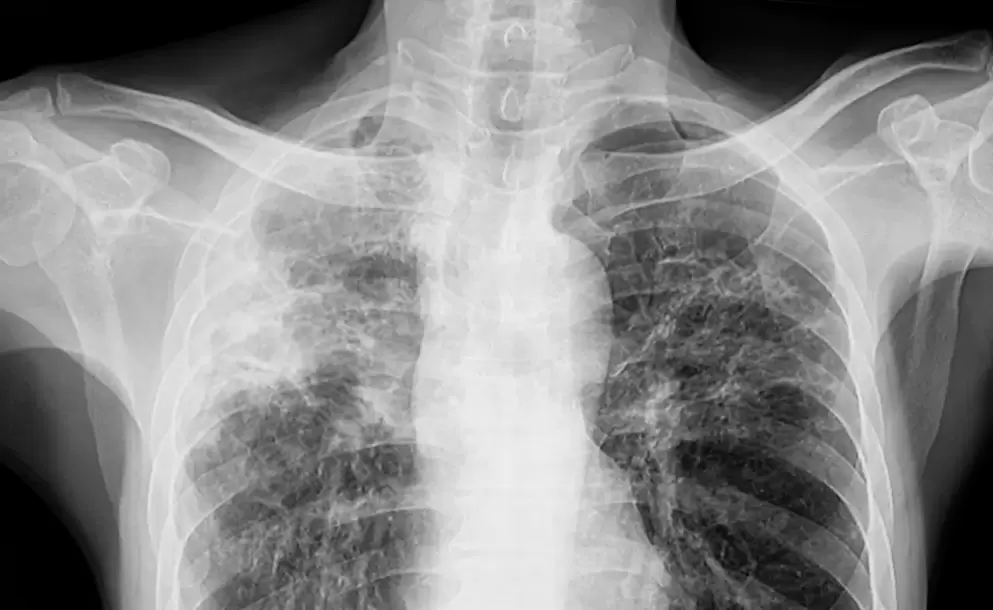

Un reciente caso de tuberculosis confirmado en un estudiante de sexto año de un colegio privado de Mar del Plata puso en alerta a la comunidad educativa. El diagnóstico fue realizado por el Programa Municipal de Control de Tuberculosis, dependiente de la Secretaría de Salud, lo que activó de inmediato los protocolos establecidos para contener posibles contagios.